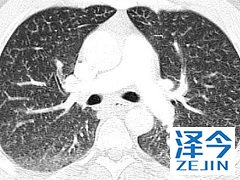

尼达尼布是一种小分子抗肿瘤多激酶抑制剂 尼达尼布已经被授予治疗特发性肺纤维化的孤儿药物,能够通过降低用力肺活量,减少疾病对患者的影响。不过不建议中重度的肝病患者使用,如果患者不确定自己是否能够使用,请在医生的指导下进行使用,并且在使用药物之前应做好避孕措施。

在3项随机,双盲,安慰剂对照临床试验(n = 1,231)中,使用尼达尼布治疗的特发性肺纤维化(IPF)患者的FVC年降低率(-60至-115 mL)显着降低。在调整性别,身高和年龄后,安慰剂(-191至-240 mL)。在3项临床试验中的2项中,尼达尼布也改善了52周内从基线开始的用力肺活量(FVC)变化百分比。II期和III期临床试验表明,与安慰剂相比,使用尼达尼布(HR 0.16; 95%CI,0.04至0.71)的患者首次急性IPF恶化的风险显着降低; 第三次临床试验(第三阶段)发现治疗组之间没有差异。尼达尼布不会影响全因死亡率。